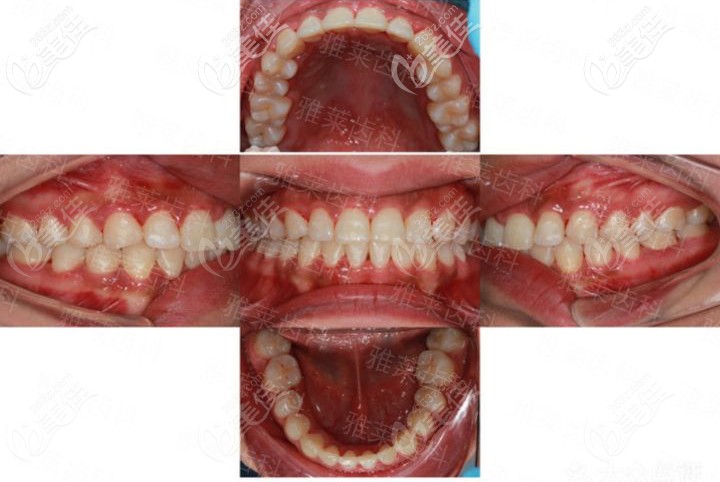

杭州雅萊齒科紀亞梅是杭州有名的牙齒矯正醫(yī)生,找她看牙靠譜嗎? b1231 G0 V0

杭州雅萊齒科紀亞梅是杭州有名的正畸醫(yī)生,很多人關(guān)注她,如果找他做隱形矯正不知道靠譜嗎?有沒有案例可參考。